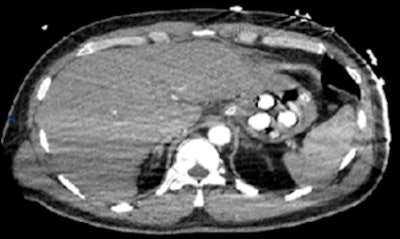

In one case, a 43-year-old man presented with an out of hospital cardiac arrest upon arrival at the airport. After being transferred to A&E, he was resuscitated and a CT pulmonary angiogram was performed to exclude a pulmonary embolism. No embolism was demonstrated, but four well-defined radiopaque densities (~300 Hounsfield units) were identified in the stomach.

CT pulmonary angiogram of a 43-year-old man who presented with an out of hospital cardiac arrest. No embolism was detected, but four well-defined radiopaque densities (~300 Hounsfield units) were identified in the stomach. All images courtesy of Drs. Nirav Bhatt and Sheena McLaggan."Gastroscopy was subsequently performed, which confirmed four white pill-shaped packets," the researchers recalled. "Two empty bags from burst packaging were removed. One of the foreign objects was removed with a two-prong balloon grasper."

The patient then underwent laparotomy for surgical removal of three packets from the fundus of the stomach. Unfortunately, the patient was unable to recover and died, and a toxicology screen confirmed the presence of cocaine.